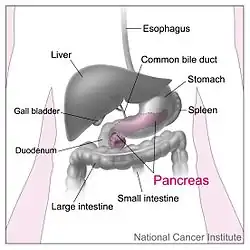

The pancreas (plural pancreases, or pancreata) is an organ of the digestive system and endocrine system of vertebrates. In humans, it is located in the abdomen behind the stomach and functions as a gland. The pancreas is a mixed or heterocrine gland, i.e., it has both an endocrine and a digestive exocrine function.[2] Ninety-nine percent of the pancreas is exocrine and 1% is endocrine.[3][4][5][6] As an endocrine gland, it functions mostly to regulate blood sugar levels, secreting the hormones insulin, glucagon, somatostatin and pancreatic polypeptide. As a part of the digestive system, it functions as an exocrine gland secreting pancreatic juice into the duodenum through the pancreatic duct. This juice contains bicarbonate, which neutralizes acid entering the duodenum from the stomach; and digestive enzymes, which break down carbohydrates, proteins and fats in food entering the duodenum from the stomach.

The pancreas is an organ that in humans lies in the abdomen, stretching from behind the stomach to the left upper abdomen near the spleen. In adults, it is about 12–15 centimetres (4.7–5.9 in) long, lobulated, and salmon-coloured in appearance.[7]

Anatomically, the pancreas is divided into a head, neck, body, and tail. The pancreas stretches from the inner curvature of the duodenum, where the head surrounds two blood vessels: the superior mesenteric artery and vein. The longest part of the pancreas, the body, stretches across behind the stomach, and the tail of the pancreas ends adjacent to the spleen.[7]

The body is the largest part of the pancreas, and mostly lies behind the stomach, tapering along its length. The peritoneum sits on top of the body of the pancreas, and the transverse colon in front of the peritoneum.[7] Behind the pancreas are several blood vessels, including the aorta, the splenic vein, and the left renal vein, as well as the beginning of the superior mesenteric artery.[7] Below the body of the pancreas sits some of the small intestine, specifically the last part of the duodenum and the jejunum to which it connects, as well as the suspensory ligament of the duodenum which falls between these two. In front of the pancreas sits the transverse colon.[8]